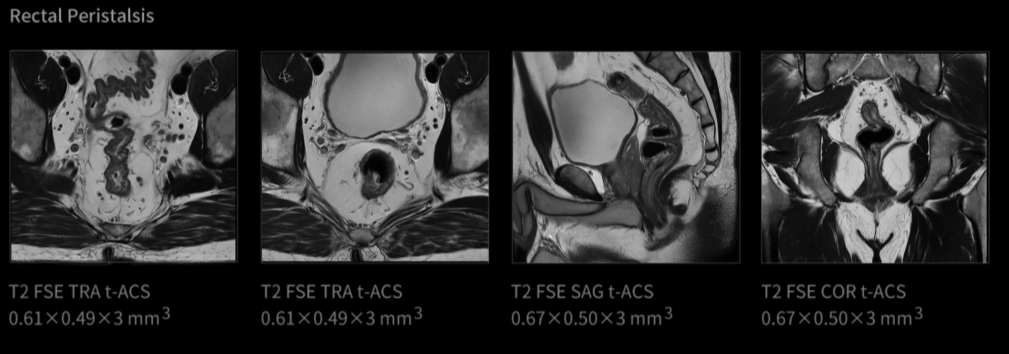

Od vzniku magnetické rezonance je pohyb jednou z největších výzev při zobrazování. Celá desetiletí byly v tomto odvětví zkoumány různé technologie pro „zmrazení pohybu“. Inovace uMR Ultra dnes slibuje svět MRI bez omezení pohybu – oblast, ve které můžeme pozorovat skutečný stav lidského těla. Jelikož otevíráme novou dimenzi zobrazování pomocí MR, je komplexní transformace diagnostických standardů nevyhnutelná.

UMR Ultra je vybaven nejmodernější technologií, která poskytuje výjimečné zobrazovací schopnosti a zaručuje přesné a konzistentní výsledky v širokém spektru klinických aplikací. Jeho pokročilý zobrazovací systém nabízí jasnost a přesnost od hlavy až po paty a tvoří základ spolehlivé diagnózy. Zařízení uMR Ultra, podporované nejmodernějším hardwarem a inovativním softwarem, zlepšuje klinické pracovní postupy a přispívá k průlomovým objevům i ke zlepšení péče o pacienty.